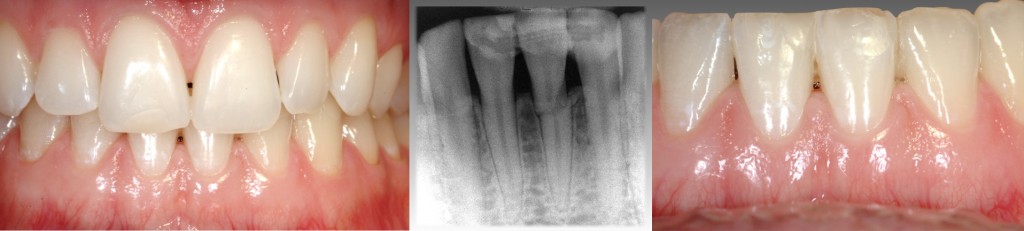

Imagine if this were your new patient:

The tooth had been traumatically fractured and bonded back in place with a Ribbond composite splint. The tooth is asymptomatic when you see the patient. What would you do? Would the discussion revolve around extraction and implant placement utilizing a small diameter implant or a resin-bonded bridge? Or would you leave the tooth and monitor the patient over time? How predictable is a tooth like this in the long term?

It’s not uncommon for a tooth like this to be extracted from looking at and treating the radiographic appearance. However, if we look at the dental literature on the prognosis of horizontal root fractures, we may decide that the tooth should be retained.